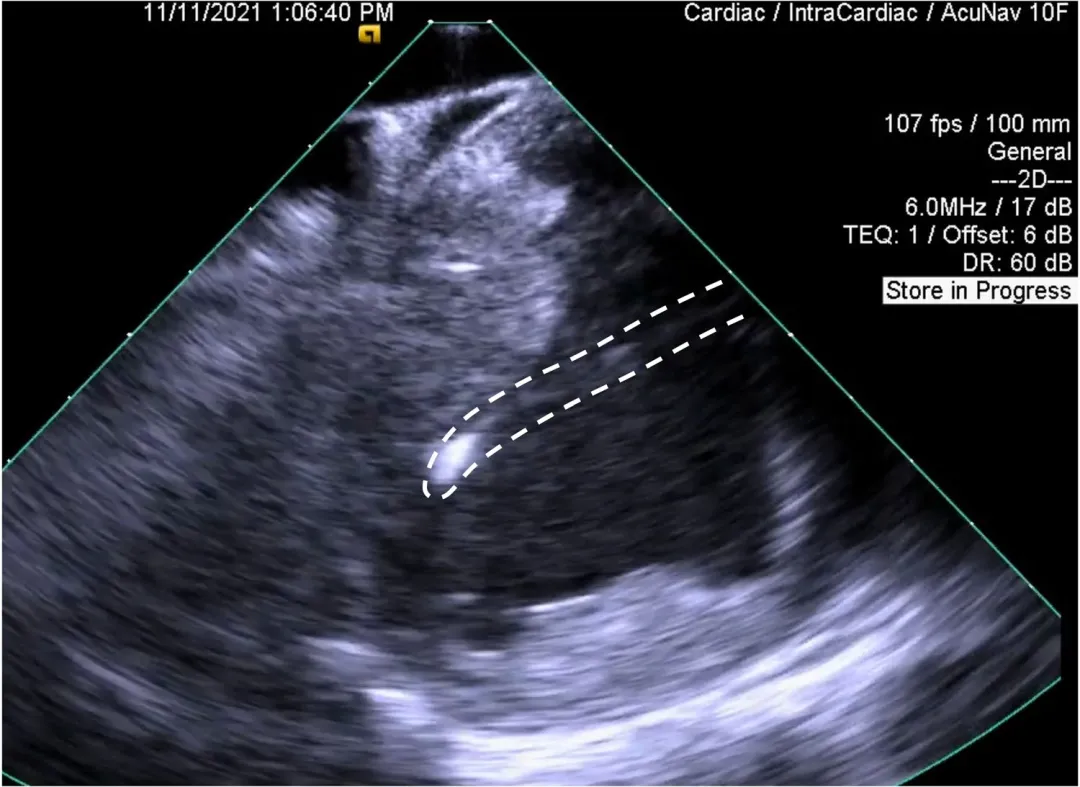

在 ICE 上观察,消融前导管冲洗速度为 4 ml/min 时观察到罕见微泡。在 PFA 消融期间和之后,微泡的出现频率没有定性增加。在通过消融导管腔接受 0.5 和 1 ml 空气微泡的 2 只阳性对照猪中,在 ICE 上观察到微泡突然和短暂增加。一只猪出现短暂性 ST 段升高,在 1 分钟内消退。

虚线表示微泡行进路径